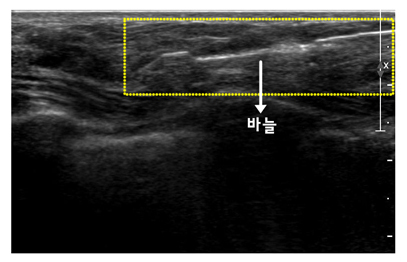

맘모톰 조직 검사는 조직을 확보하는데 어려움이 있었던 기존의 방법을 개선한 검사법입니다. 기존의 방법과 달리 병소에 바늘을 한번 위치시킨 후 반복적으로 여러 번 원하는 양의 조직을 얻을 수 있으며 수술 조직검사만큼 정확합니다.

영상 유도 하에 굵은 바늘(11 또는 8게이지)을 병소에 넣고 진공 흡입기를 작동하여 바늘 안으로 조직을 끌어들인 후 바늘 내부의 회전칼을 작동시켜 자동으로 병변을 잘라 유방 밖으로 배출해주는 최신 조직검사 방법입니다. 암이 의심되는 경우는 조직 검사 목적으로 이용되지만, 병변이 최대 직경 3cm이하의 양성 종양으로 병소를 제거하기를 원하는 경우에는 큰 흉터 없이 그 병변을 완전히 제거할 수 있어 양성 종양의 치료목적으로 사용됩니다.

[ 맘모톰 조직검사 ]

[ 맘모톰 조직검사 시술 사진 ]